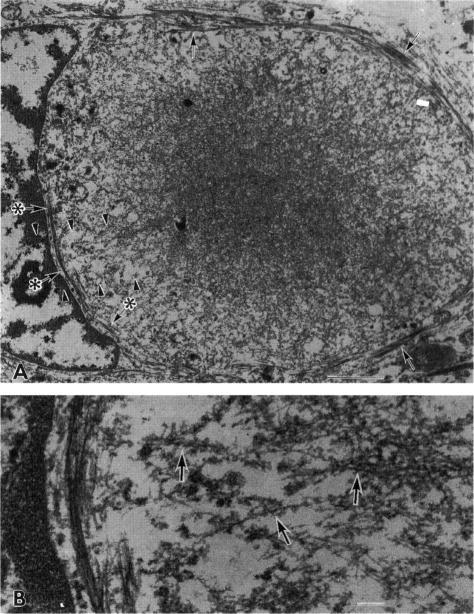

To clarify the pathological characteristics of astrocytic hyaline inclusions (Ast-HIs) in patients with familial amyotrophic lateral sclerosis (FALS) with neuronal Lewy-body-like hyaline inclusions (LBHIs), eight autopsies on members of four different families, including two long-term surviving patients with clinical courses of over 10 years, were analyzed. Ast-HIs were found only in the two long-term surviving patients who belonged to different families and to different races. Ast-HIs were ultrastructurally composed of 15- to 25-nm granule-coated fibrils that had immunoreactivities to superoxide dismutase 1 (SOD1) and ubiquitin. Approximately 50% of the Ast-HIs expressed alpha B-crystallin, metallothionein, glutamine synthetase, and tubulin (alpha and beta) at various intensities. Some Ast-HIs reacted with antibodies to tau protein, S-100 protein, and heat shock protein 27. The Ast-HIs were not stained for glial fibrillary acidic protein. Our results suggest a cooperative role of superoxide dismutase 1, ubiquitin, and cytoskeletal proteins in the formation of granule-coated fibrils (namely, Ast-HIs) and provide evidence that Ast-HIs are formed in certain long-surviving familial amyotrophic lateral sclerosis patients with neuronal Lewy-body-like hyaline inclusions.